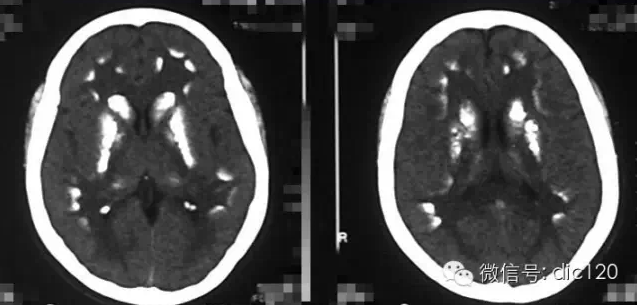

診斷小腦萎縮通常需要進(jìn)行神經(jīng)系統(tǒng)檢查、影像學(xué)檢查(如腦部CT或MRI)和實(shí)驗(yàn)室測試,治療小腦萎縮的方法主要包括藥物治療、物理治療和康復(fù)訓(xùn)練等,藥物治療旨在緩解癥狀和改善生活質(zhì)量,物理治療幫助患者恢復(fù)肌肉力量和運(yùn)動功能,康復(fù)訓(xùn)練則包括語言治療、認(rèn)知訓(xùn)練和心理支持等。